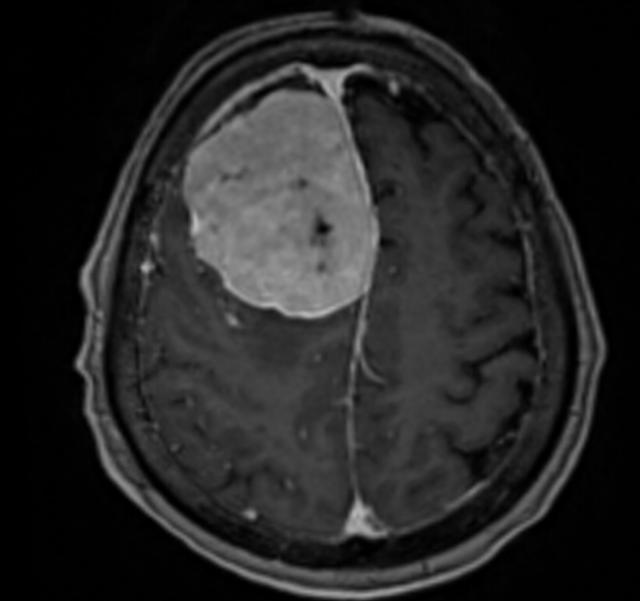

(▲患者颅内肿瘤影像)

时间回溯到年前,李奶奶被查出颅内肿瘤,且肿瘤已侵犯矢状窦、颅骨及头皮。由于年事已高,又身患多种慢性病,家属带着她辗转北京、上海多家医院求医,却均因手术风险过高被婉拒——多家医院认为,老人高龄叠加多重基础病,且长期使用抗凝药物,手术及麻醉过程中随时可能出现致命并发症,手术难度与风险远超常规。

一个月前,李奶奶病情突然恶化,出现严重食欲减退、意识模糊等症状,家属抱着最后一丝希望,将她送到湖南省第二人民医院(省脑科医院)脑血管神经外科就诊。入院检查显示,老人右额窦旁的巨大脑膜瘤已严重挤压脑组织,生命体征极不稳定。